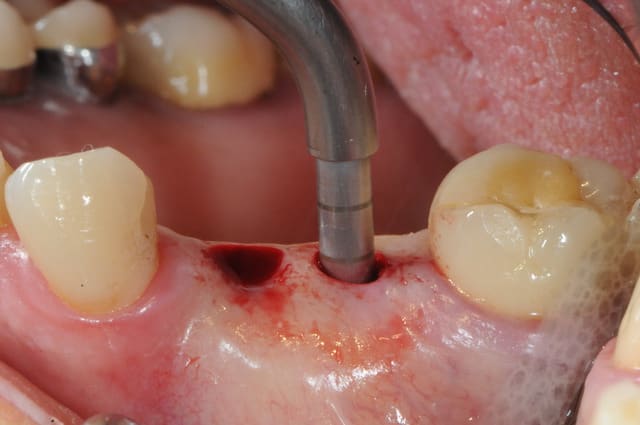

voici le dernier né de la gamme Axiom d'Anthogyr.

il a un corps conique et des spires beaucoup plus agressives pour augmenter la stabilité primaire.

son diamètre au niveau du col est légèrement réduit ce qui limite la compression crestal.

le cas que je vous présente date d'hier, il n'a rien d'extraordinaire, alors soyez indulgents, c'était juste pour le plaisir de partager ça avec vous.

3- ostéotomie-condensation

4- le nouveau foret diam 2-2.4